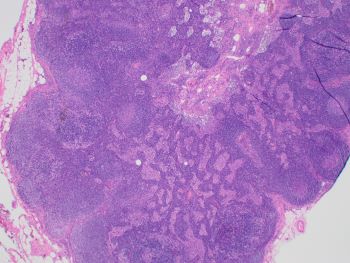

Images 1 and 2 show an enlarged lymph node with mostly intact architecture and marked paracortical expansion with pale staining areas. The expansion is mostly nodular. Although, areas of diffuse paracortical expansion are seen, such as on the left side of image 2. Images 3 and 4 show pale staining areas at high power magnification from different parts of the lymph node. Image 3 shows Langerhans and interdigitating dendritic cells with mostly small lymphocytes in the background. Image 4 shows Reed Sternberg cells with a mixed background of histiocytes, small lymphocytes, eosinophils, and plasma cells.

CHL is part of the differential diagnosis for dermatopathic lymphadenopathy (DL). The pale areas can resemble the Reed Sternberg cells and histiocytes of CHL and vice versa. An added challenge is when CHL shows an interfollicular growth pattern (seen in this case) without marked distortion of the lymph node architecture. provides an extra challenge in showing relatively preserved nodal architecture. High power examination of the pale areas for Reed Sternberg cells will distinguish the two with immunohistochemical studies performed if needed (CD15, CD30, PAX5, CD45, etc.).